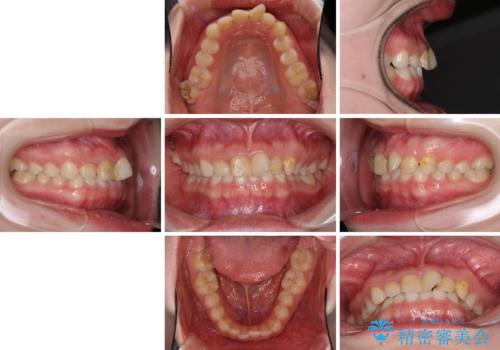

- 前歯の歯並びと虫歯を気にして来院された患者様です。

上下前歯の歯列不正はインビザラインにより歯列を整え、その後に、前歯5本をオールセラミッククラウンにて補綴治療することとしました。

矯正治療前に前歯のむし歯治療を行ったものの、樹脂で充填するには虫歯が広範囲であったため、審美的に問題がありました。